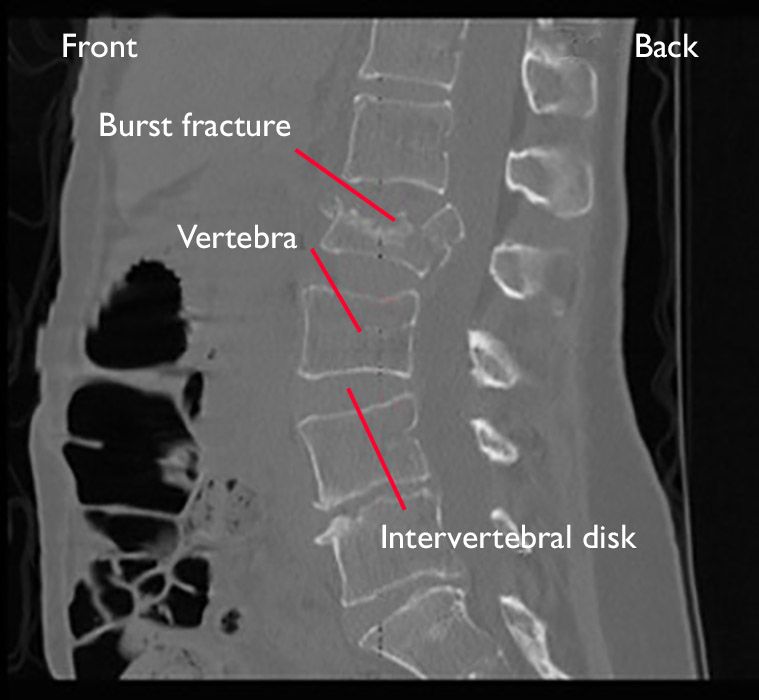

Types Of Burst Fractures . signs of a burst fracture include: The difference is what causes them. chance fractures and burst fractures are both types of spinal fractures. a burst fracture can result from spinal injury or trauma that causes the affected vertebral body to be crushed or severely compressed,. a burst fracture usually results from significant trauma that compresses the bone, such as a motor vehicle accident or a. Moderate to severe back pain made worse by moving;